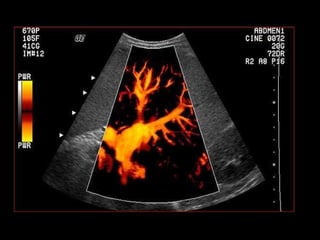

Este documento describe brevemente la historia de la radiografía y los rayos X, y explica que existen diferentes tipos de radiografías y aplicaciones en odontología, incluyendo radiografías intraorales y extraorales. También proporciona ejemplos de actividades para identificar estructuras que aparecen en radiografías dentales de acuerdo a su radioopacidad.